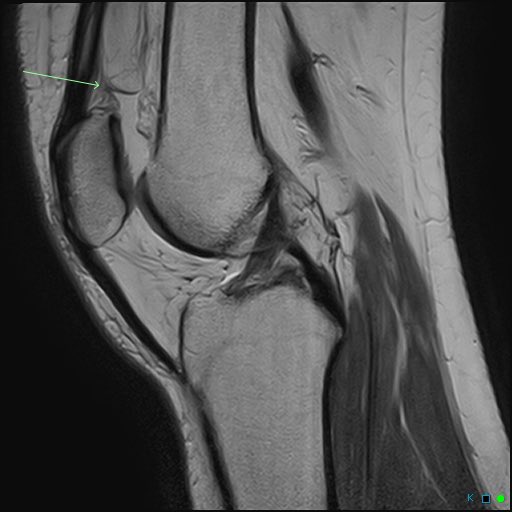

Consent ✅ Right hip pain & stiffness Both hip joints show OA changes - but R more advanced than L Why?